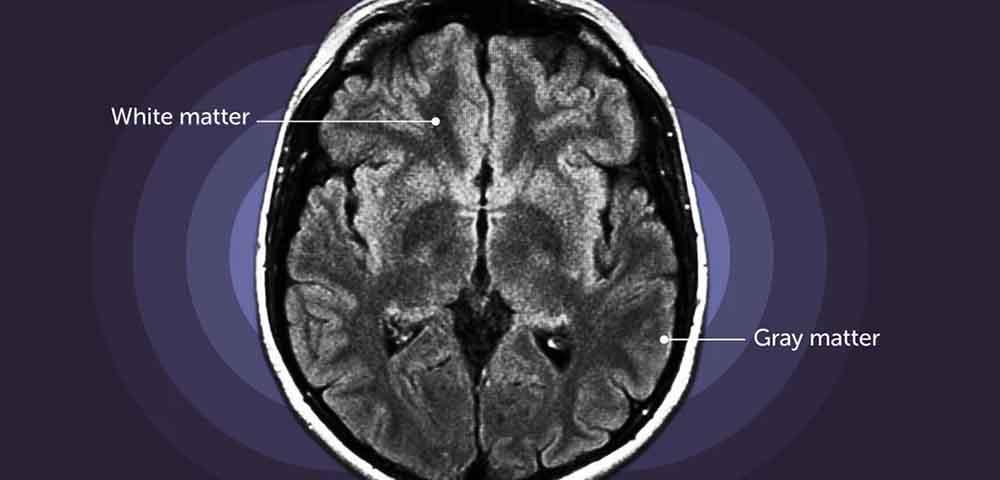

According to a recent study, the grey matter volume in pregnant women decreases by roughly five per cent and a partial recovery occurs in the postpartum phase. The brain’s outermost layer and interior are made up of grey matter, which aids in information processing and interpretation, enabling thinking, learning, and memory.

In order to examine the structural alterations that take place during the second and third trimesters, as well as the first six months after giving birth, researchers studied the MRI brain scans of around 180 first-time pregnant women. The 'baseline' consisted of scans performed before conception.

In 94 per cent of the brain, grey matter was found to have changed. This shift was most noticeable in the default mode network, which is known to support social cognition. The study was published in the journal ‘Nature Communications’. Researchers discovered that a stronger mother-infant relationship was associated with a higher recovery of grey matter.

The study’s authors also found out that a U-shaped trajectory in grey matter volume dips in late pregnancy and partially recovers during the postpartum period. The U-shaped trajectory in GM volume impacted several areas throughout the brain’s cortex, covering 94 per cent of its surface. Changes in higher-order cognitive networks, including the frontoparietal and default modes, were especially noticeable. Additionally, the study demonstrated that the alterations in the brain associated with pregnancy were linked to variations in the levels of two estrogens, ‘estriol-3-sulfate’ and ‘estrone-sulfate.’

The researchers also found that a larger decline and subsequent recovery of brain grey matter volume are associated with a higher rise and subsequent fall in estrogen levels. In order to establish that the brain alterations are primarily related to the biological process of pregnancy rather than the feeling of becoming a mother, the researchers also included ‘non-gestational mothers,’ or women whose partners became pregnant.

A 38-year-old healthy woman’s neuroanatomical changes before, during, and after pregnancy were examined in a study published in the journal ‘Nature Neuroscience’. The results showed a substantial correlation between the increase in estradiol (an estrogen) and a general decrease in grey matter. Some of the brain abnormalities reverted to levels comparable to those at two months into the pregnancy, while others were found to last for up to two years after the pregnancy ended.